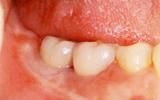

| 右の奥歯の喪失は比較的よく見られます。 | ![]() |

【術前】 |

【術後】 |